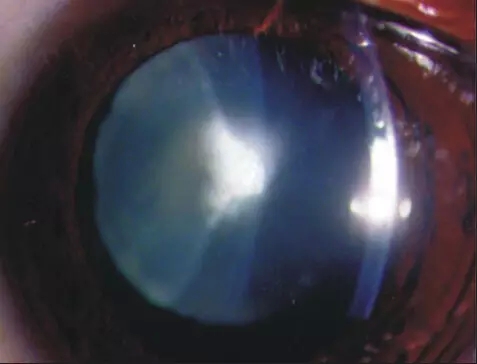

上图所示成熟期白内障,可见晶状体为完全的乳白色混浊,相应视力严重下降,它是白内障发展到成熟阶段的表现。其不具特异性,常可发生于视网膜脱离、外伤、葡萄膜炎、糖尿病等疾病。手术摘除是治疗成熟期白内障的最好方法,此外手术还可降低眼压。